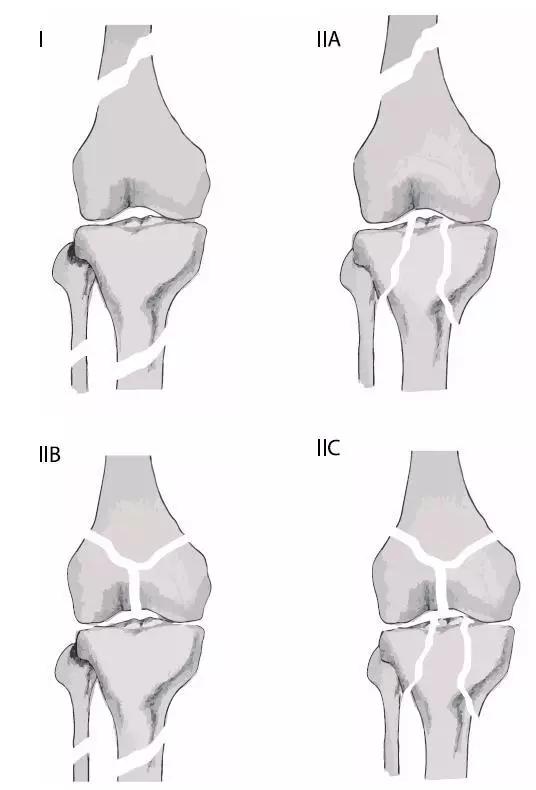

7. 浮膝

特指股骨、胫腓骨同时骨折,膝关节上下无附着而得名。其它浮髋、浮肩与此同理。

(来源:Medscape)

浮膝的 Fraser's 分型(来源:Management of the Floating Knee in Polytrauma Patients. Open Orthop J. 2015 Jul 31;9:347-55.)